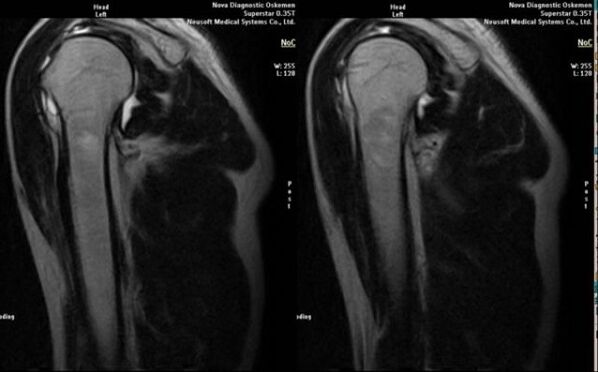

- resonancia magnética e tomografía computarizada;

Os signos que indican o desenvolvemento da artrose inclúen directamente a aparición dun estreitamento significativo do espazo articular, a esclerose das estruturas subcartilaxinosas, o adelgazamento da propia capa de condrocitos, a aparición de osteofitos e a deposición de cristais de sal no líquido intraarticular.